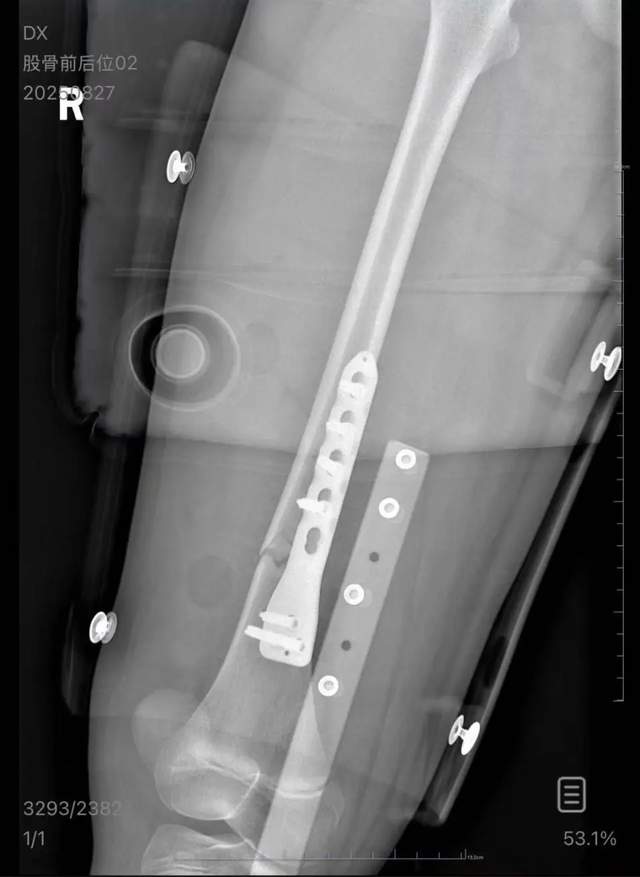

事后得知,该男子本欲下车,因折返取眼镜时列车晃动,失手从上铺跌落,正中女孩右腿。医院诊断令人揪心:右股骨粉碎性骨折。救护车疾驰、手术灯亮起,一场突如其来的灾难,彻底改变了这个家庭的暑假。